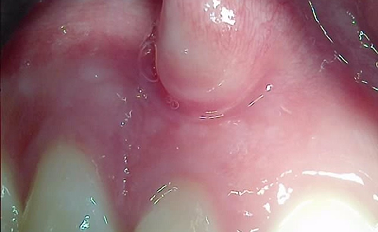

즉시식립 임플란트

다른 치과에서는 기다리라 했지만, 하루임플에서는 즉시 임플란트 식립으로